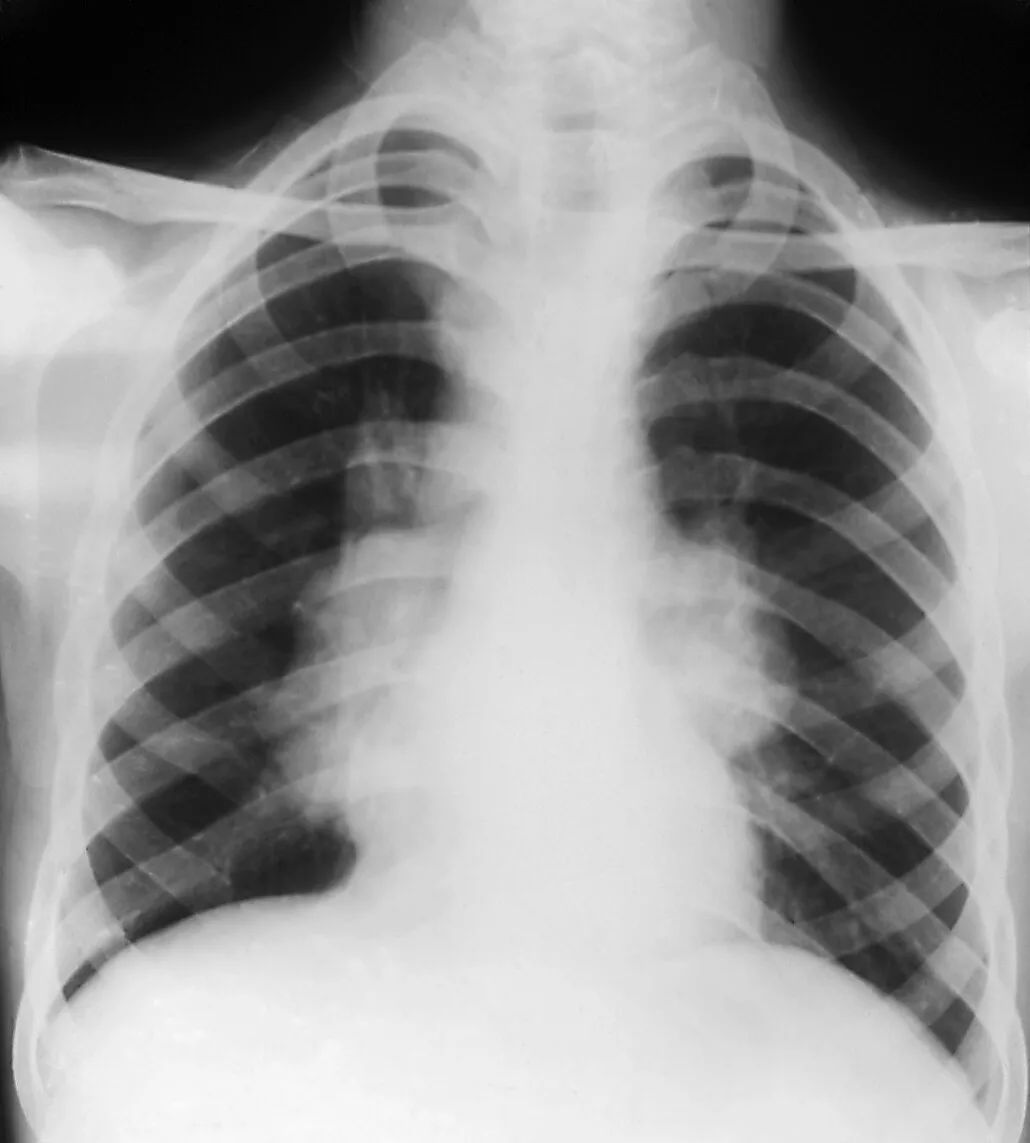

肺结节长在身体里悄无声息,没有任何症状,几乎所有发现肺结节的病人都是体检发现,或者因其他原因检查时无意中发现。不少网友会向我咨询:我肩膀疼会不会是肺结节引起的?我胸闷不舒服是不是肺结节引起的?我胸痛半个月了是不是肺结节导致的?可以肯定的说,这所有的症状与肺结节都关系不大。但值得一提的是,肺结节手术之后却有可能出现一些症状,而且有些症状会持续较长时间。